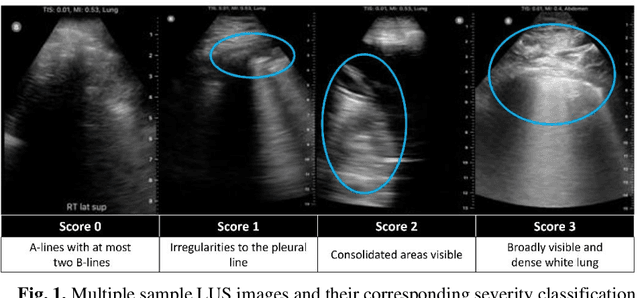

Abstract:Artificial intelligence-based analysis of lung ultrasound imaging has been demonstrated as an effective technique for rapid diagnostic decision support throughout the COVID-19 pandemic. However, such techniques can require days- or weeks-long training processes and hyper-parameter tuning to develop intelligent deep learning image analysis models. This work focuses on leveraging 'off-the-shelf' pre-trained models as deep feature extractors for scoring disease severity with minimal training time. We propose using pre-trained initializations of existing methods ahead of simple and compact neural networks to reduce reliance on computational capacity. This reduction of computational capacity is of critical importance in time-limited or resource-constrained circumstances, such as the early stages of a pandemic. On a dataset of 49 patients, comprising over 20,000 images, we demonstrate that the use of existing methods as feature extractors results in the effective classification of COVID-19-related pneumonia severity while requiring only minutes of training time. Our methods can achieve an accuracy of over 0.93 on a 4-level severity score scale and provides comparable per-patient region and global scores compared to expert annotated ground truths. These results demonstrate the capability for rapid deployment and use of such minimally-adapted methods for progress monitoring, patient stratification and management in clinical practice for COVID-19 patients, and potentially in other respiratory diseases.